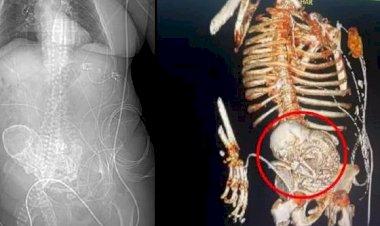

Após o acidente, Welington auxiliou no socorro junto a um médico que estava no local, encaminhando a vítima ao Hospital Municipal. No Pronto-Socorro, conforme consta no processo, o médico plantonista informou que o estado de saúde era grave, com traumatismo craniano e presença de coágulo, exigindo cirurgia em menos de 24 horas.

Ainda segundo o documento, o profissional alertou que a vítima não resistiria à espera pela autorização do Sistema Único de Saúde. Diante da urgência, Welington entrou em contato com o Hospital Med Barra, em Barra do Garças, município localizado a 511 quilômetros de Cuiabá, e autorizou a cirurgia de forma particular, além da internação em unidade de terapia intensiva.

O pagamento foi realizado no dia 13 de outubro de 2021, totalizando R$ 35 mil. Desse valor, R$ 4 mil corresponderam à internação em UTI e R$ 31 mil aos serviços médicos e hospitalares prestados à vítima. As notas fiscais foram anexadas ao processo.